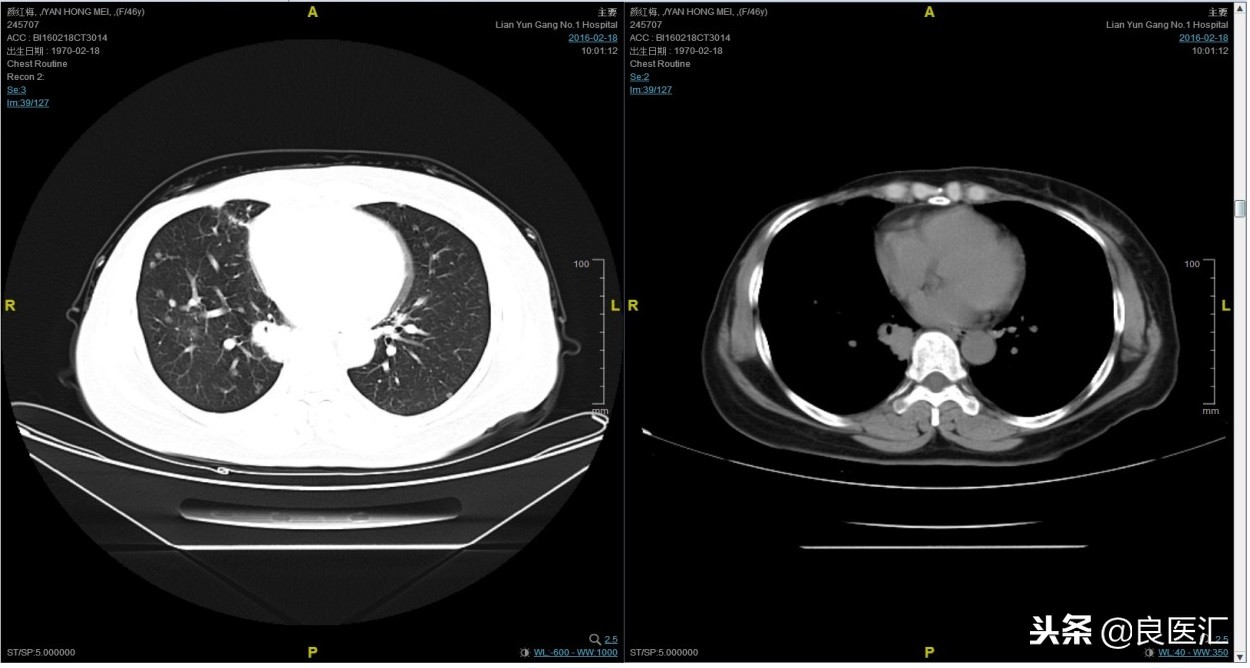

随访至2016-2-18,肺部病灶进展,肺内转移病灶增多。PFS2=10个月。

三线解救治疗及评价

从2016-2-19开始给予紫杉醇+曲妥珠单抗治疗,紫杉醇240mg,3周重复,曲妥珠单抗330mg三周重复。患者末次应用曲妥珠单抗和紫杉醇时间为2016-6-24,紫杉醇共应用4周期。